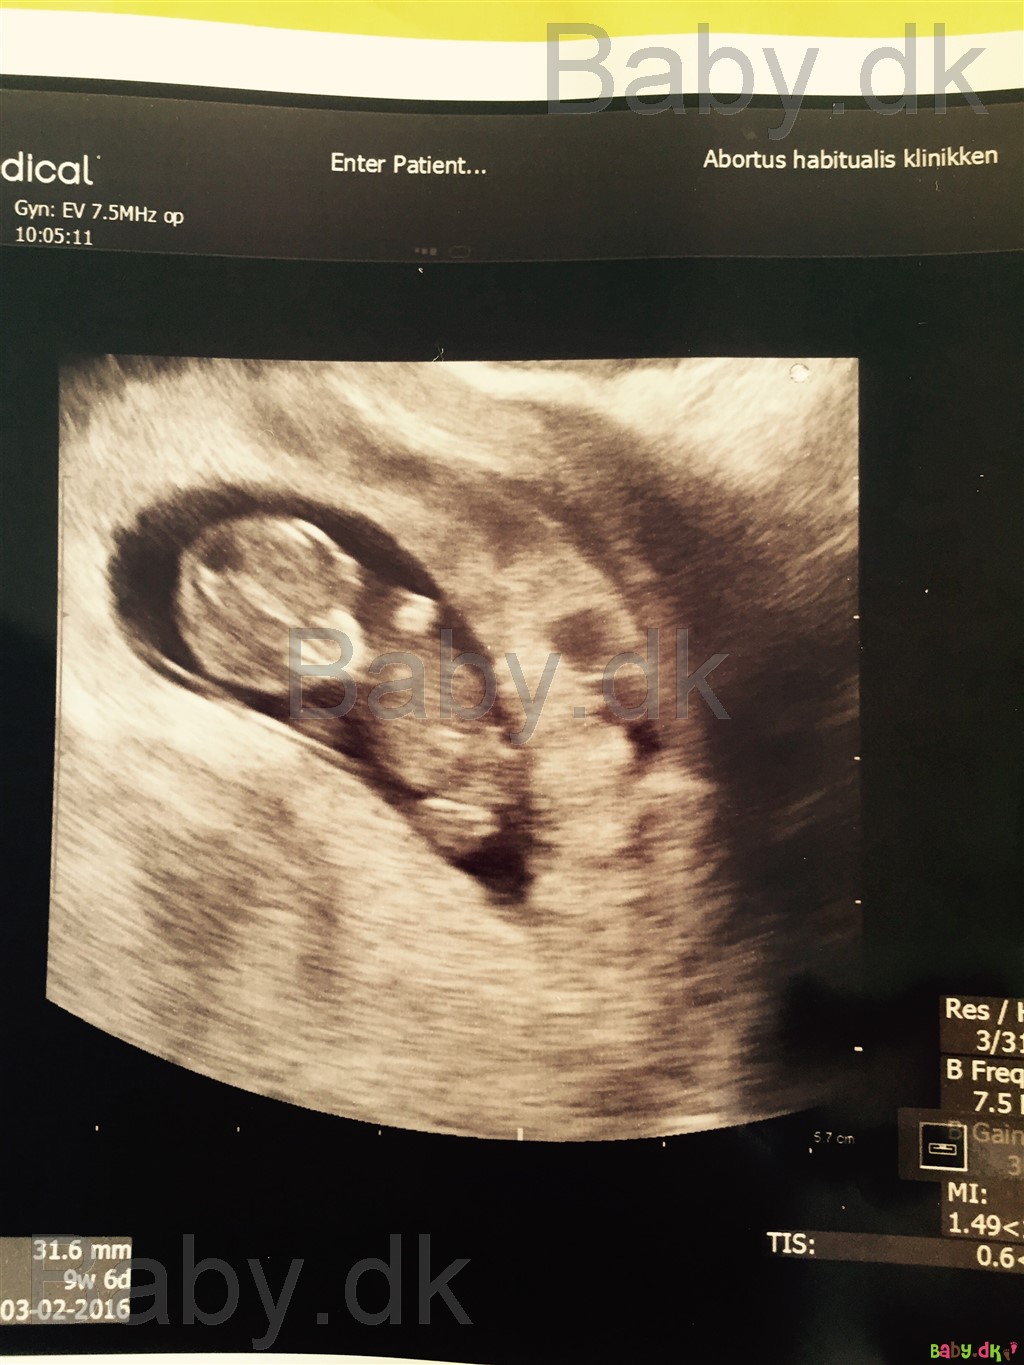

Den gik rigtig godt

Mit skønne brombær <3

Skal scannes igen på riget den 20/7 og så NF på Hvidovre den 29/7 :-)

Jeg er 11+0 i morgen, så vildt som ugerne flyver afsted